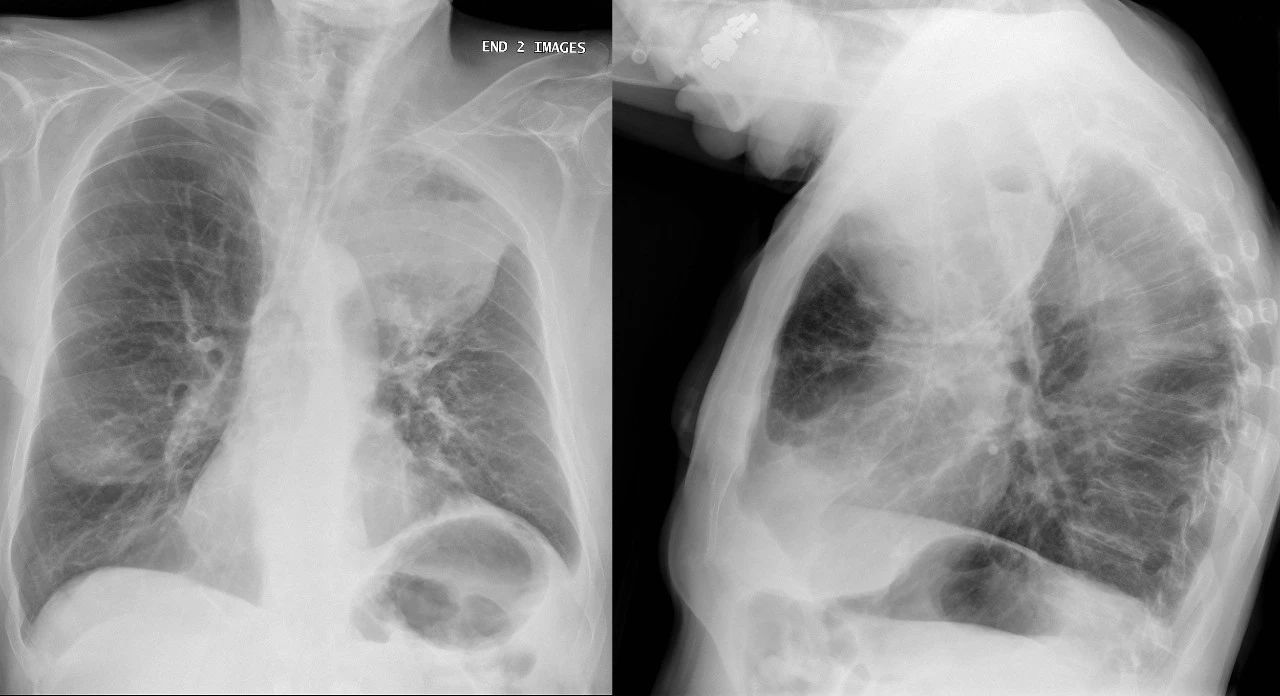

2016年,著名生物杂志Cell就发表了一项研究表明,吸烟会阻塞关键的免疫细胞,延缓它们的行动,阻碍它们对抗感染的能力。正因如此,吸烟者往往面临更大的肺结核(TB)风险,感染后的病情也更为严重[4]。